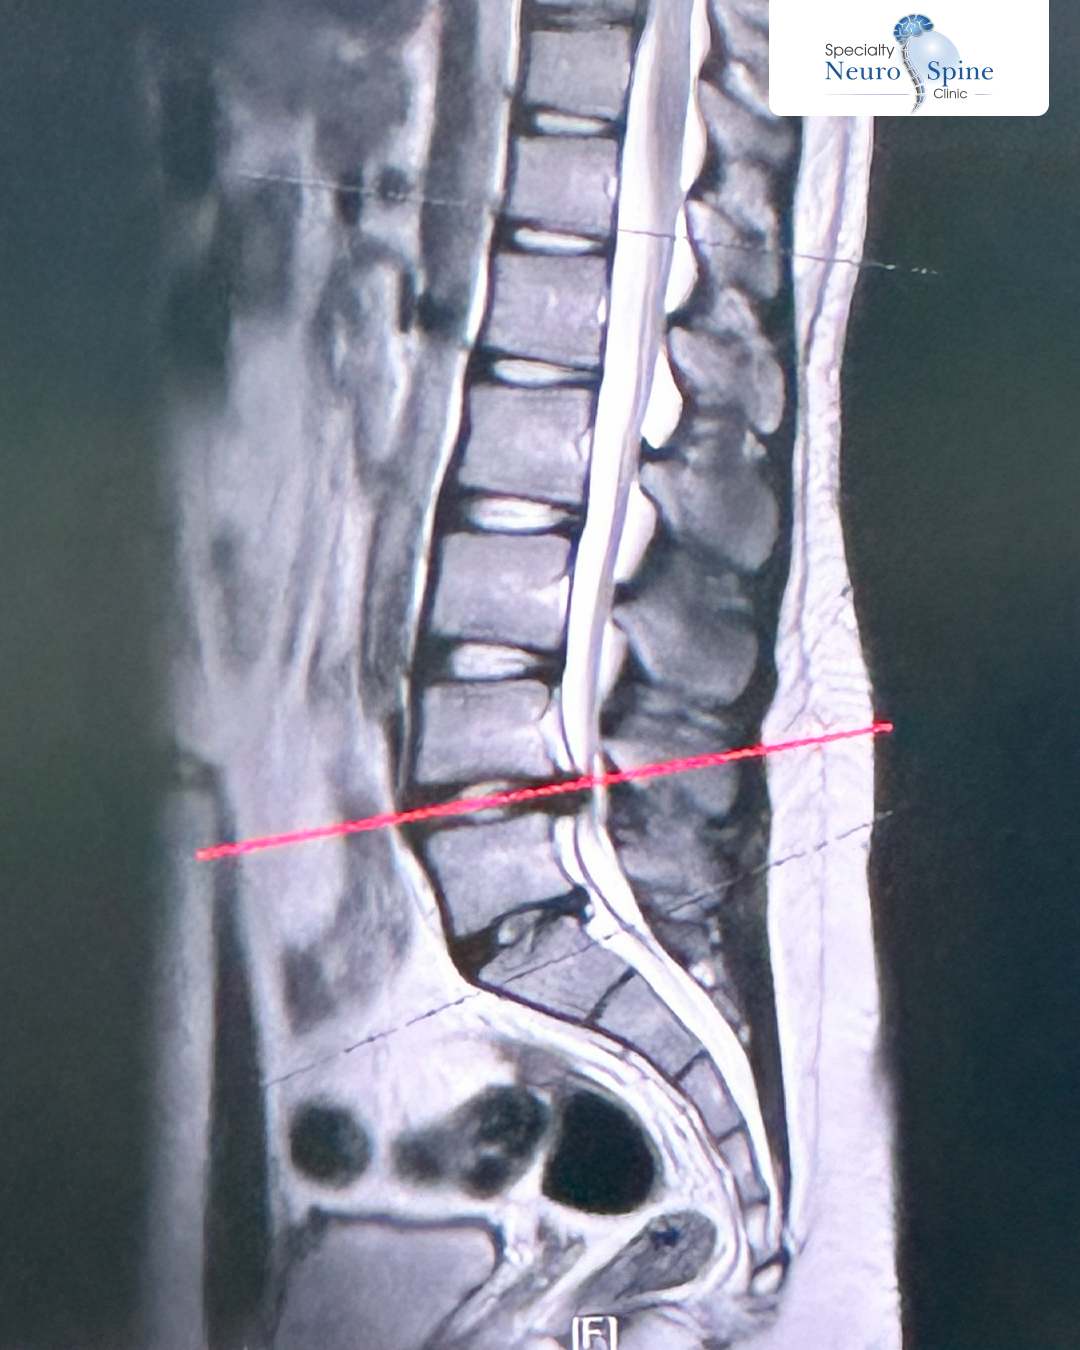

صورة الأشعة لمريضنا الشاب محمد، 21 عاماً من الأدرن، توضح الضغط على العصب الناتج عن الانزلاق الغضروفي بين الفقرة القَطَنية الرابعة والخامسة.